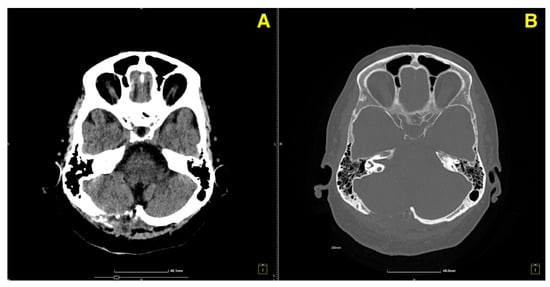

Clinically, the patient continued to demonstrate full recovery, with no neurological deficits. Coordination tests remained normal, and there was no recurrence of her vertigo or gait instability. Given these findings, the patient was discharged from regular follow-up, with instructions for routine imaging in the future as part of long-term surveillance. At the 1-year follow-up, a control CT scan (Figure 5) was performed to assess the long-term stability of the surgical site and ensure that no delayed complications had arisen.

Figure 5. One-year follow-up control CT. (A): Axial CT image displays the postoperative region in the right cerebellar hemisphere, showing well-preserved stability with no residual cavernoma or evidence of delayed complications, such as hemorrhage or fluid accumulation. The surrounding cerebellar tissue remains intact and unaffected. (B): Coronal CT image highlights the absence of recurrent lesions or structural abnormalities at the surgical site. The cavity remains unchanged, reflecting long-term postoperative success without any signs of new pathological findings.

The patient remained asymptomatic and fully functional at the 1-year mark, with no recurrence of vertiginous symptoms or neurological deficits. Based on these findings, the patient was advised to continue with routine imaging as part of long-term surveillance, but no further immediate follow-up was deemed necessary given the stable postoperative course.